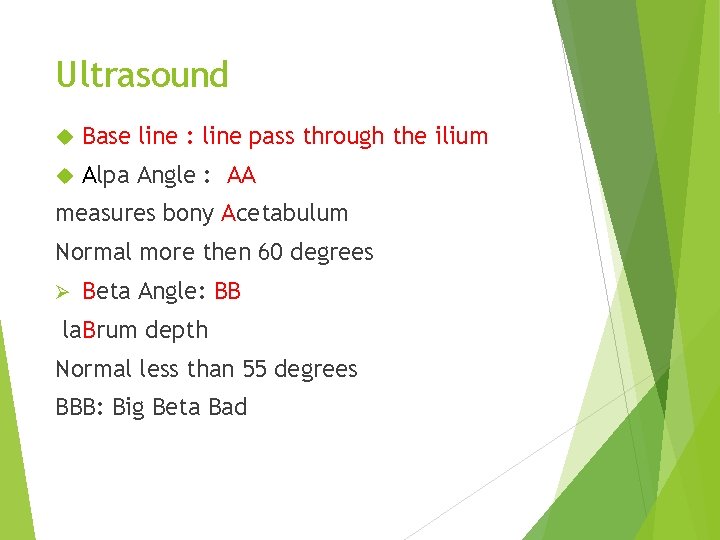

Ultrasound Base line : line pass through the ilium Alpa Angle : AA measures bony Acetabulum Normal more then 60 degrees Ø Beta Angle: BB la. Brum depth Normal less than 55 degrees BBB: Big Beta Bad